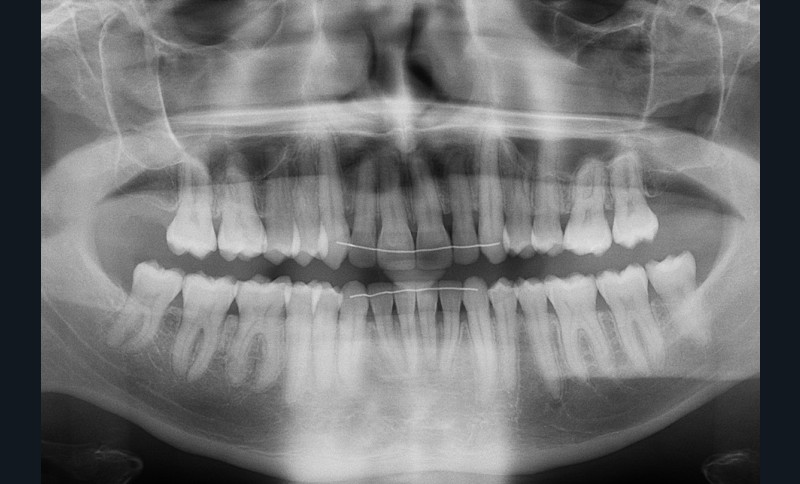

Diagnostic (fig. 1a-i)

Le patient consulte initialement pour des défauts d’alignement. L’examen clinique confirme l’existence d’un encombrement antérieur bimaxillaire, mais révèle aussi la présence d’une Classe II dentaire sévère, d’une exoclusion de la 27 et de troubles parodontaux (peu ou absence de papilles inter-dentaires). Sur le plan squelettique, le patient est relativement équilibré avec un profil harmonieux.